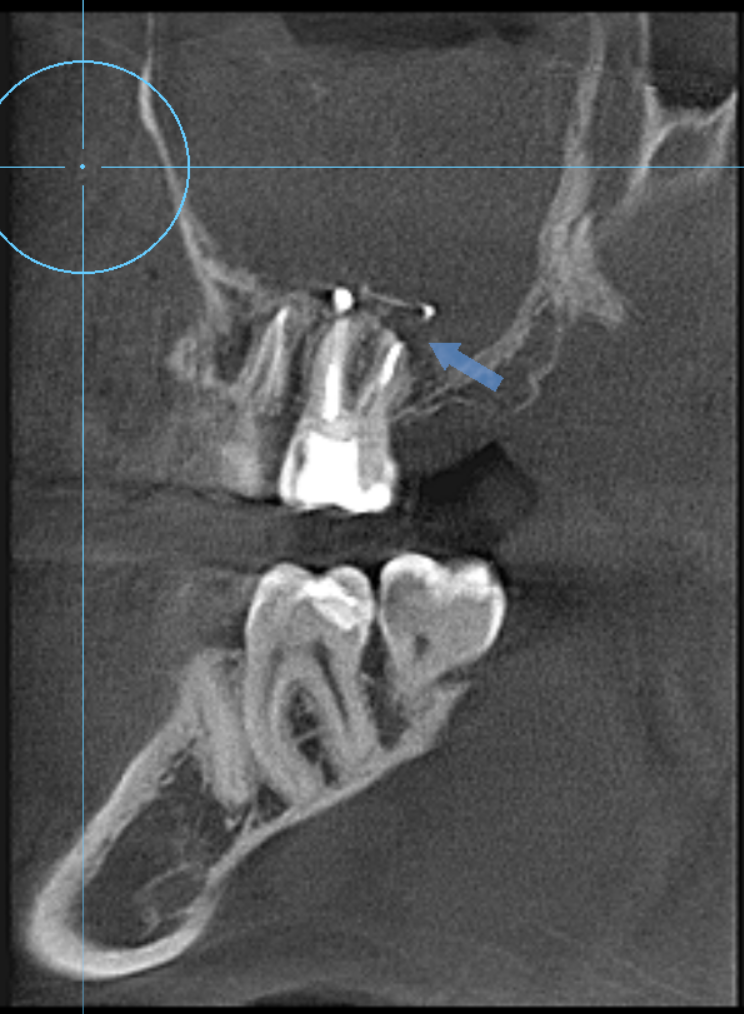

Здравствуйте, на КТ заполнена пазуха справа, каналы 6 и 7 зубов лечились давно, думаю больше 5+ лет, зубы не беспокоят.

- 6 и 7 перелечить, не поможет - резекция, если все пойдет хорошо, потом поставить коронки;

- 6 перелечить, временная пломба, понаблюдать, если не поможет - резекция, поставить постоянную пломбу, 7 удалить;

- 6 сразу апикальная хирургия, 7 удалить;

- оба удалить, залечить пазуху, поставить импланты;

- оба удалить + сразу эндоскопическая микрогайморотомия под общим наркозом (через нос, если не ошибаюсь);

- оба удалить + сразу (микро)гайморотомия через ту же рану под местной анестезией